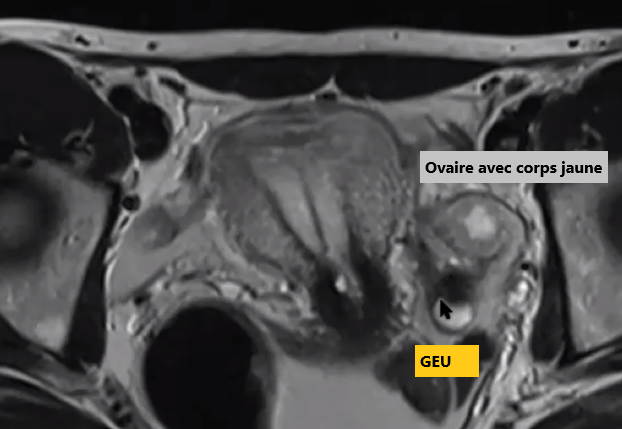

- Masse Paraovarienne ++ (Souvent un corps j’aune dans l’ovaire)

- 97% dans la trompe distale (chercher masse près de l’ovaire)

IRM

- Masse avec cavité liquidienne

- Hemosalpinx

- Caillots de sang et hémoperitoine